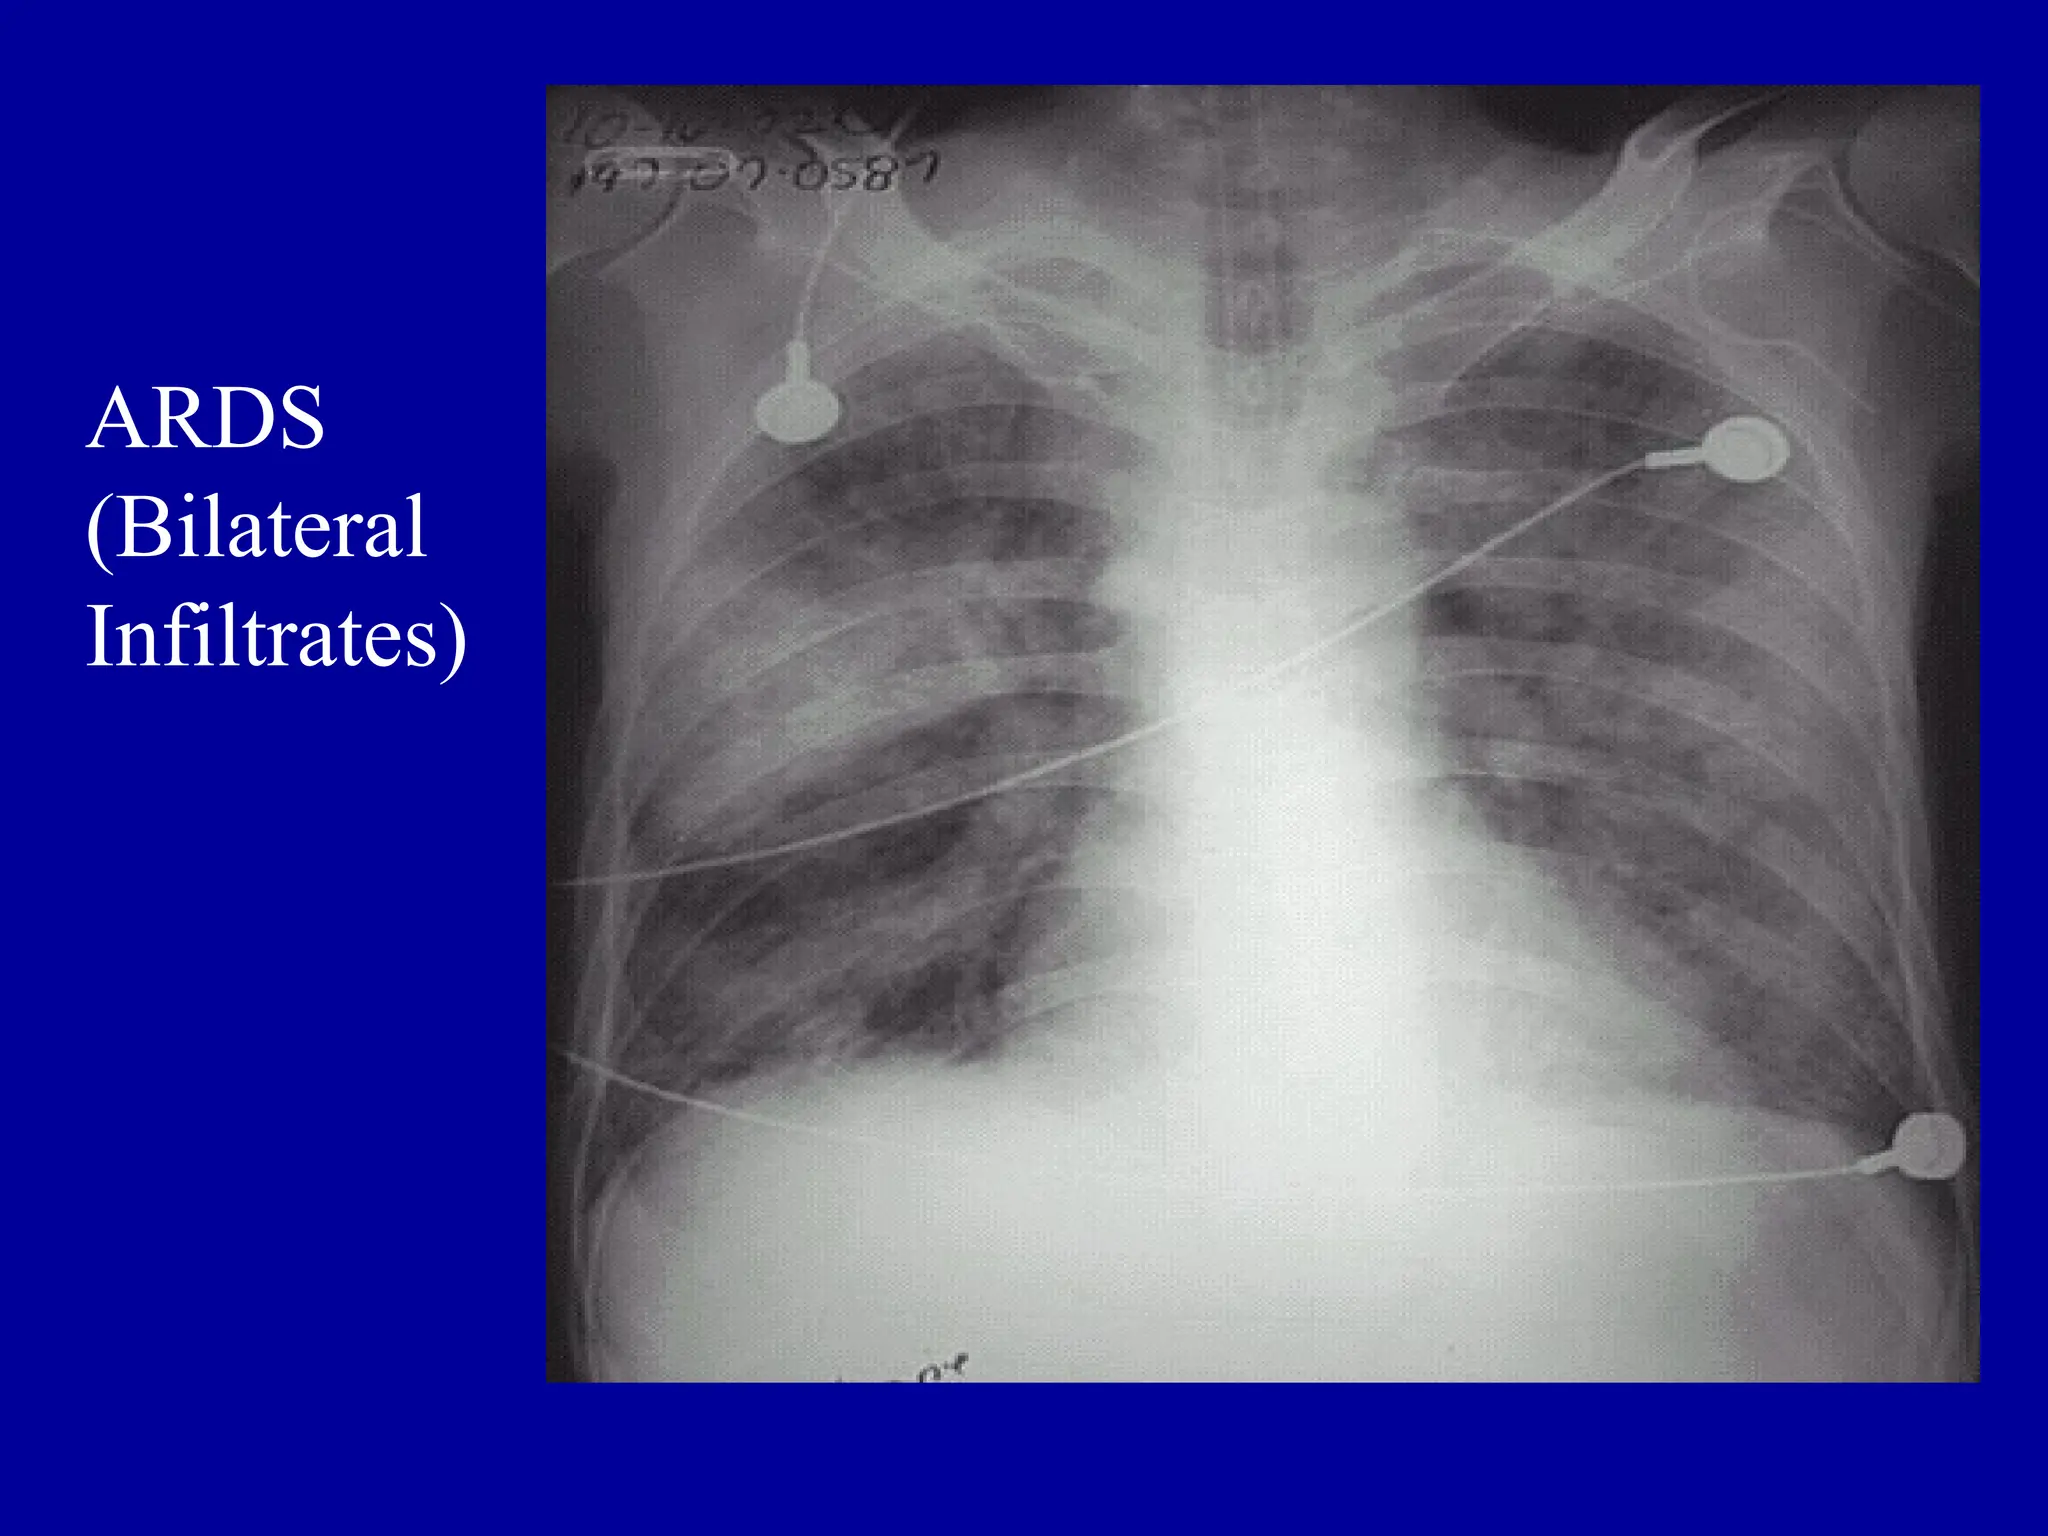

ARDS

(Bilateral

Infiltrates)